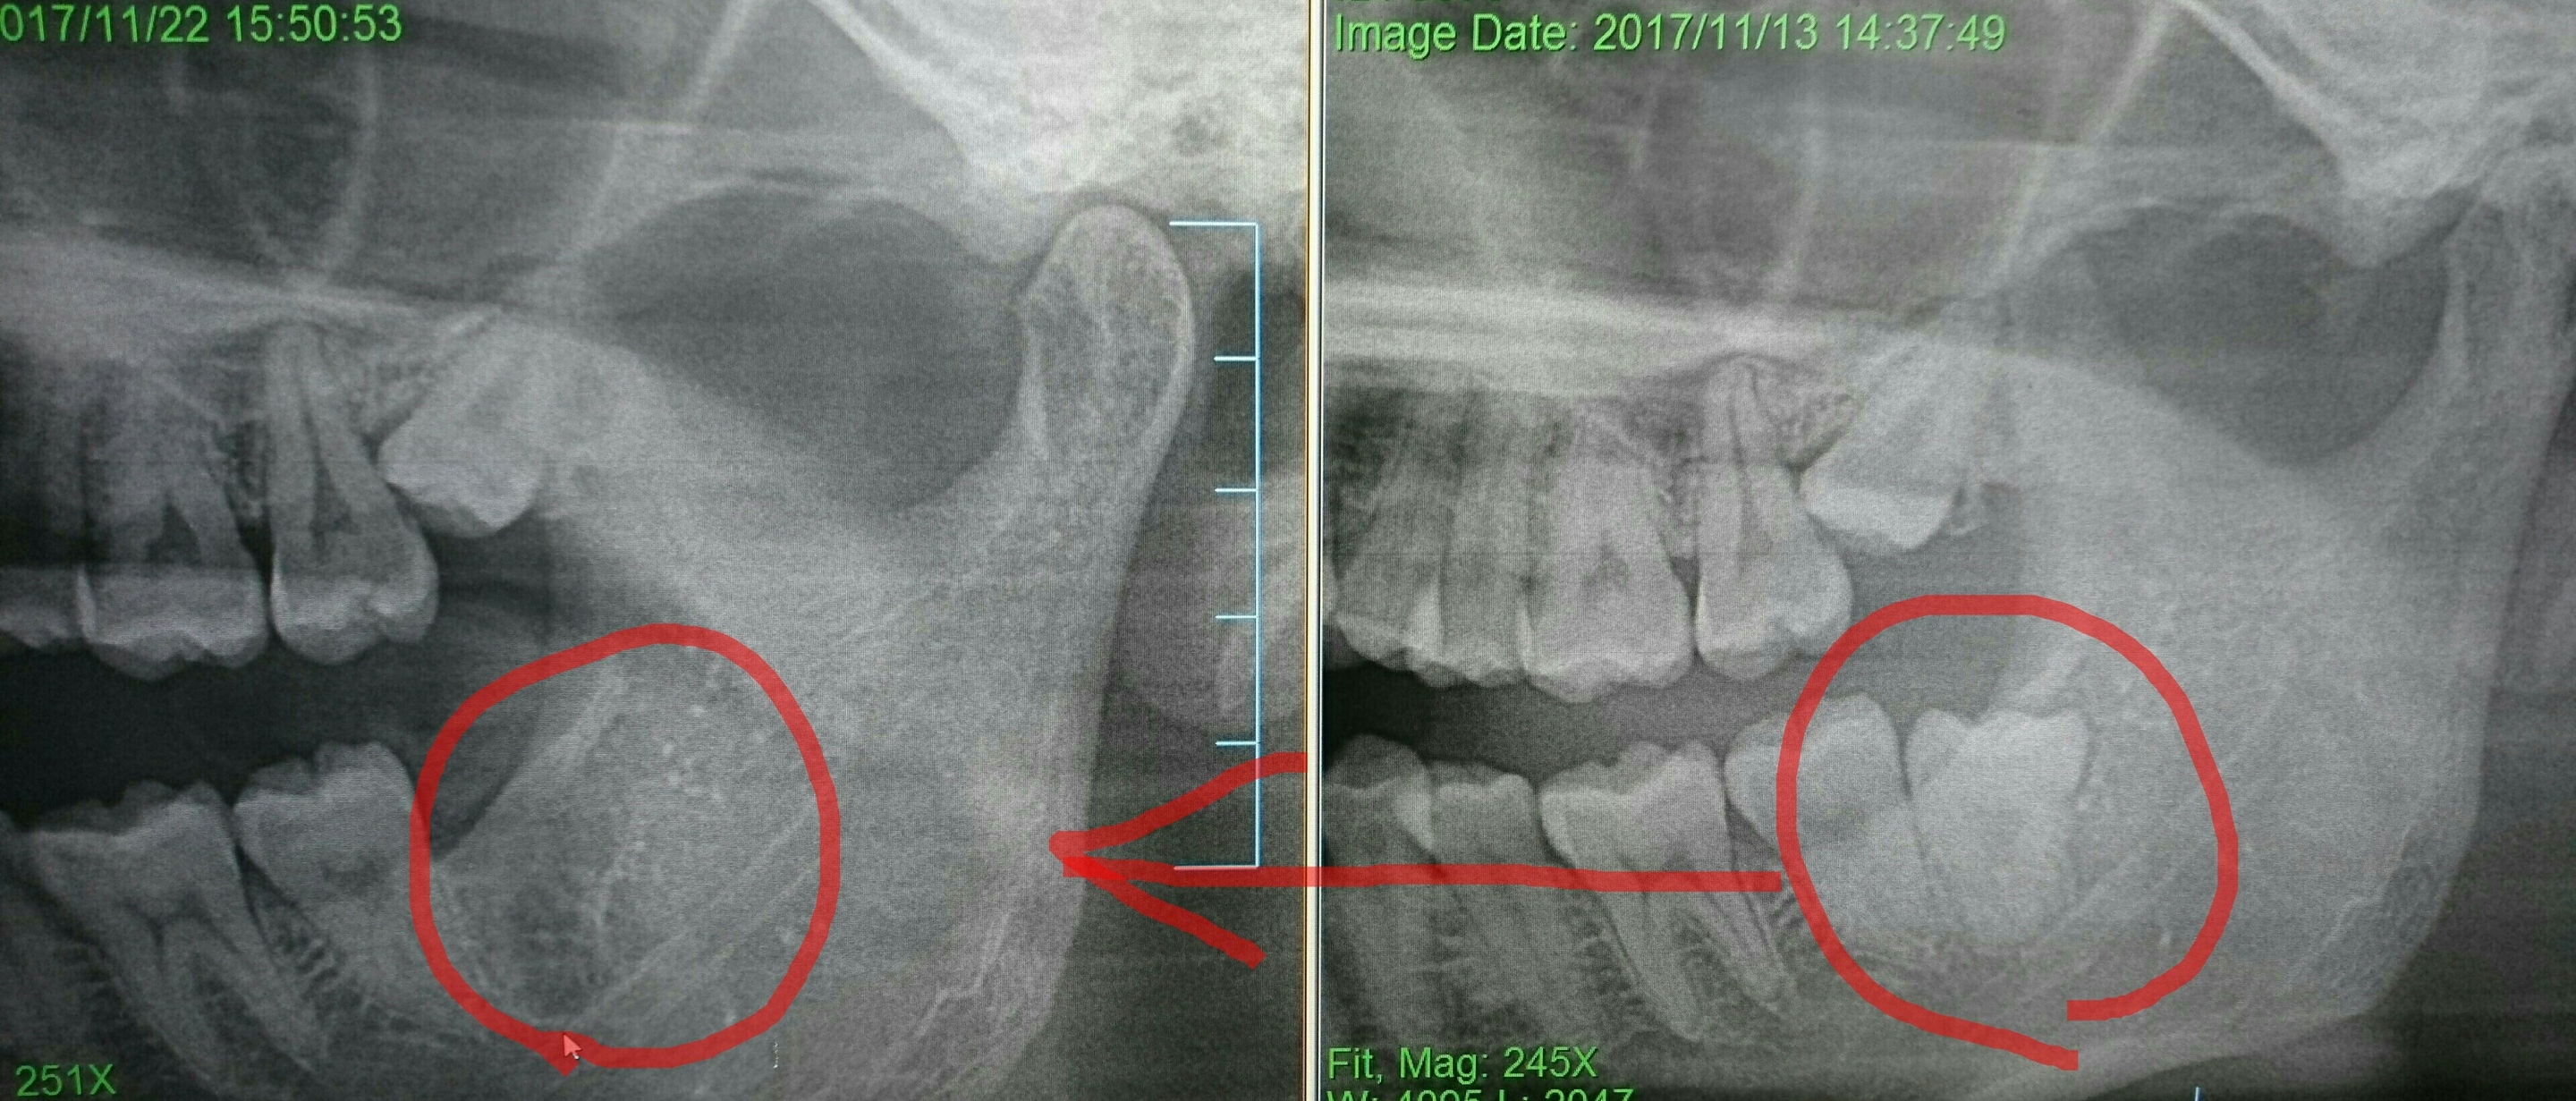

親知らずの抜歯にはCTが不可欠な事は以前もお話ししました。また、過度な血管損傷や組織の挫滅がなければ痛み、腫れ、出血もほぼほぼありません。しかし最近では親知らずが水平に斜めにはえている、根っこが複雑、神経血管に近い、口が開かないため器具が入らない。痛みを最小限にしたい などのために、親知らずの頭だけ取って根っこを残す施術があります。(コロネクトミー❗)

詳しくはお気軽にご相談下さい。(症例によります)

下のレントゲン写真をみると頭を取った根っこの回りに辛うじて骨が出来ている(骨添加)様子が分かります。